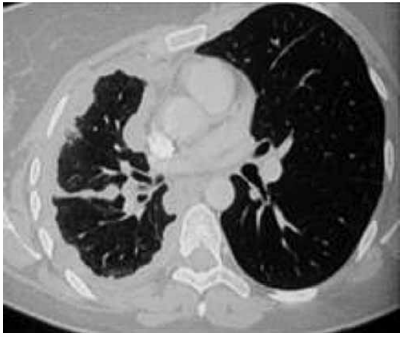

Paciente com 67 anos, tabagista, procura atendimento

em unidade de pronto atendimento. Relata dor precordial e nas costas, há quatro meses, inicialmente de leve

intensidade, mas que está piorando, além de fraqueza

nos membros inferiores e desconforto para engolir. Há

três dias, percebeu inchaço no pescoço, dos dois lados.

Exame físico: hemodinamicamente estável, pletora facial

moderada, edema supraclavicular bilateral, circulação

colateral na metade superior do tórax.

Radiografia de tórax a seguir:

O quadro clínico apresentado permite a elaboração de hipótese diagnóstica e de possível conduta, que devem ser, respectivamente: